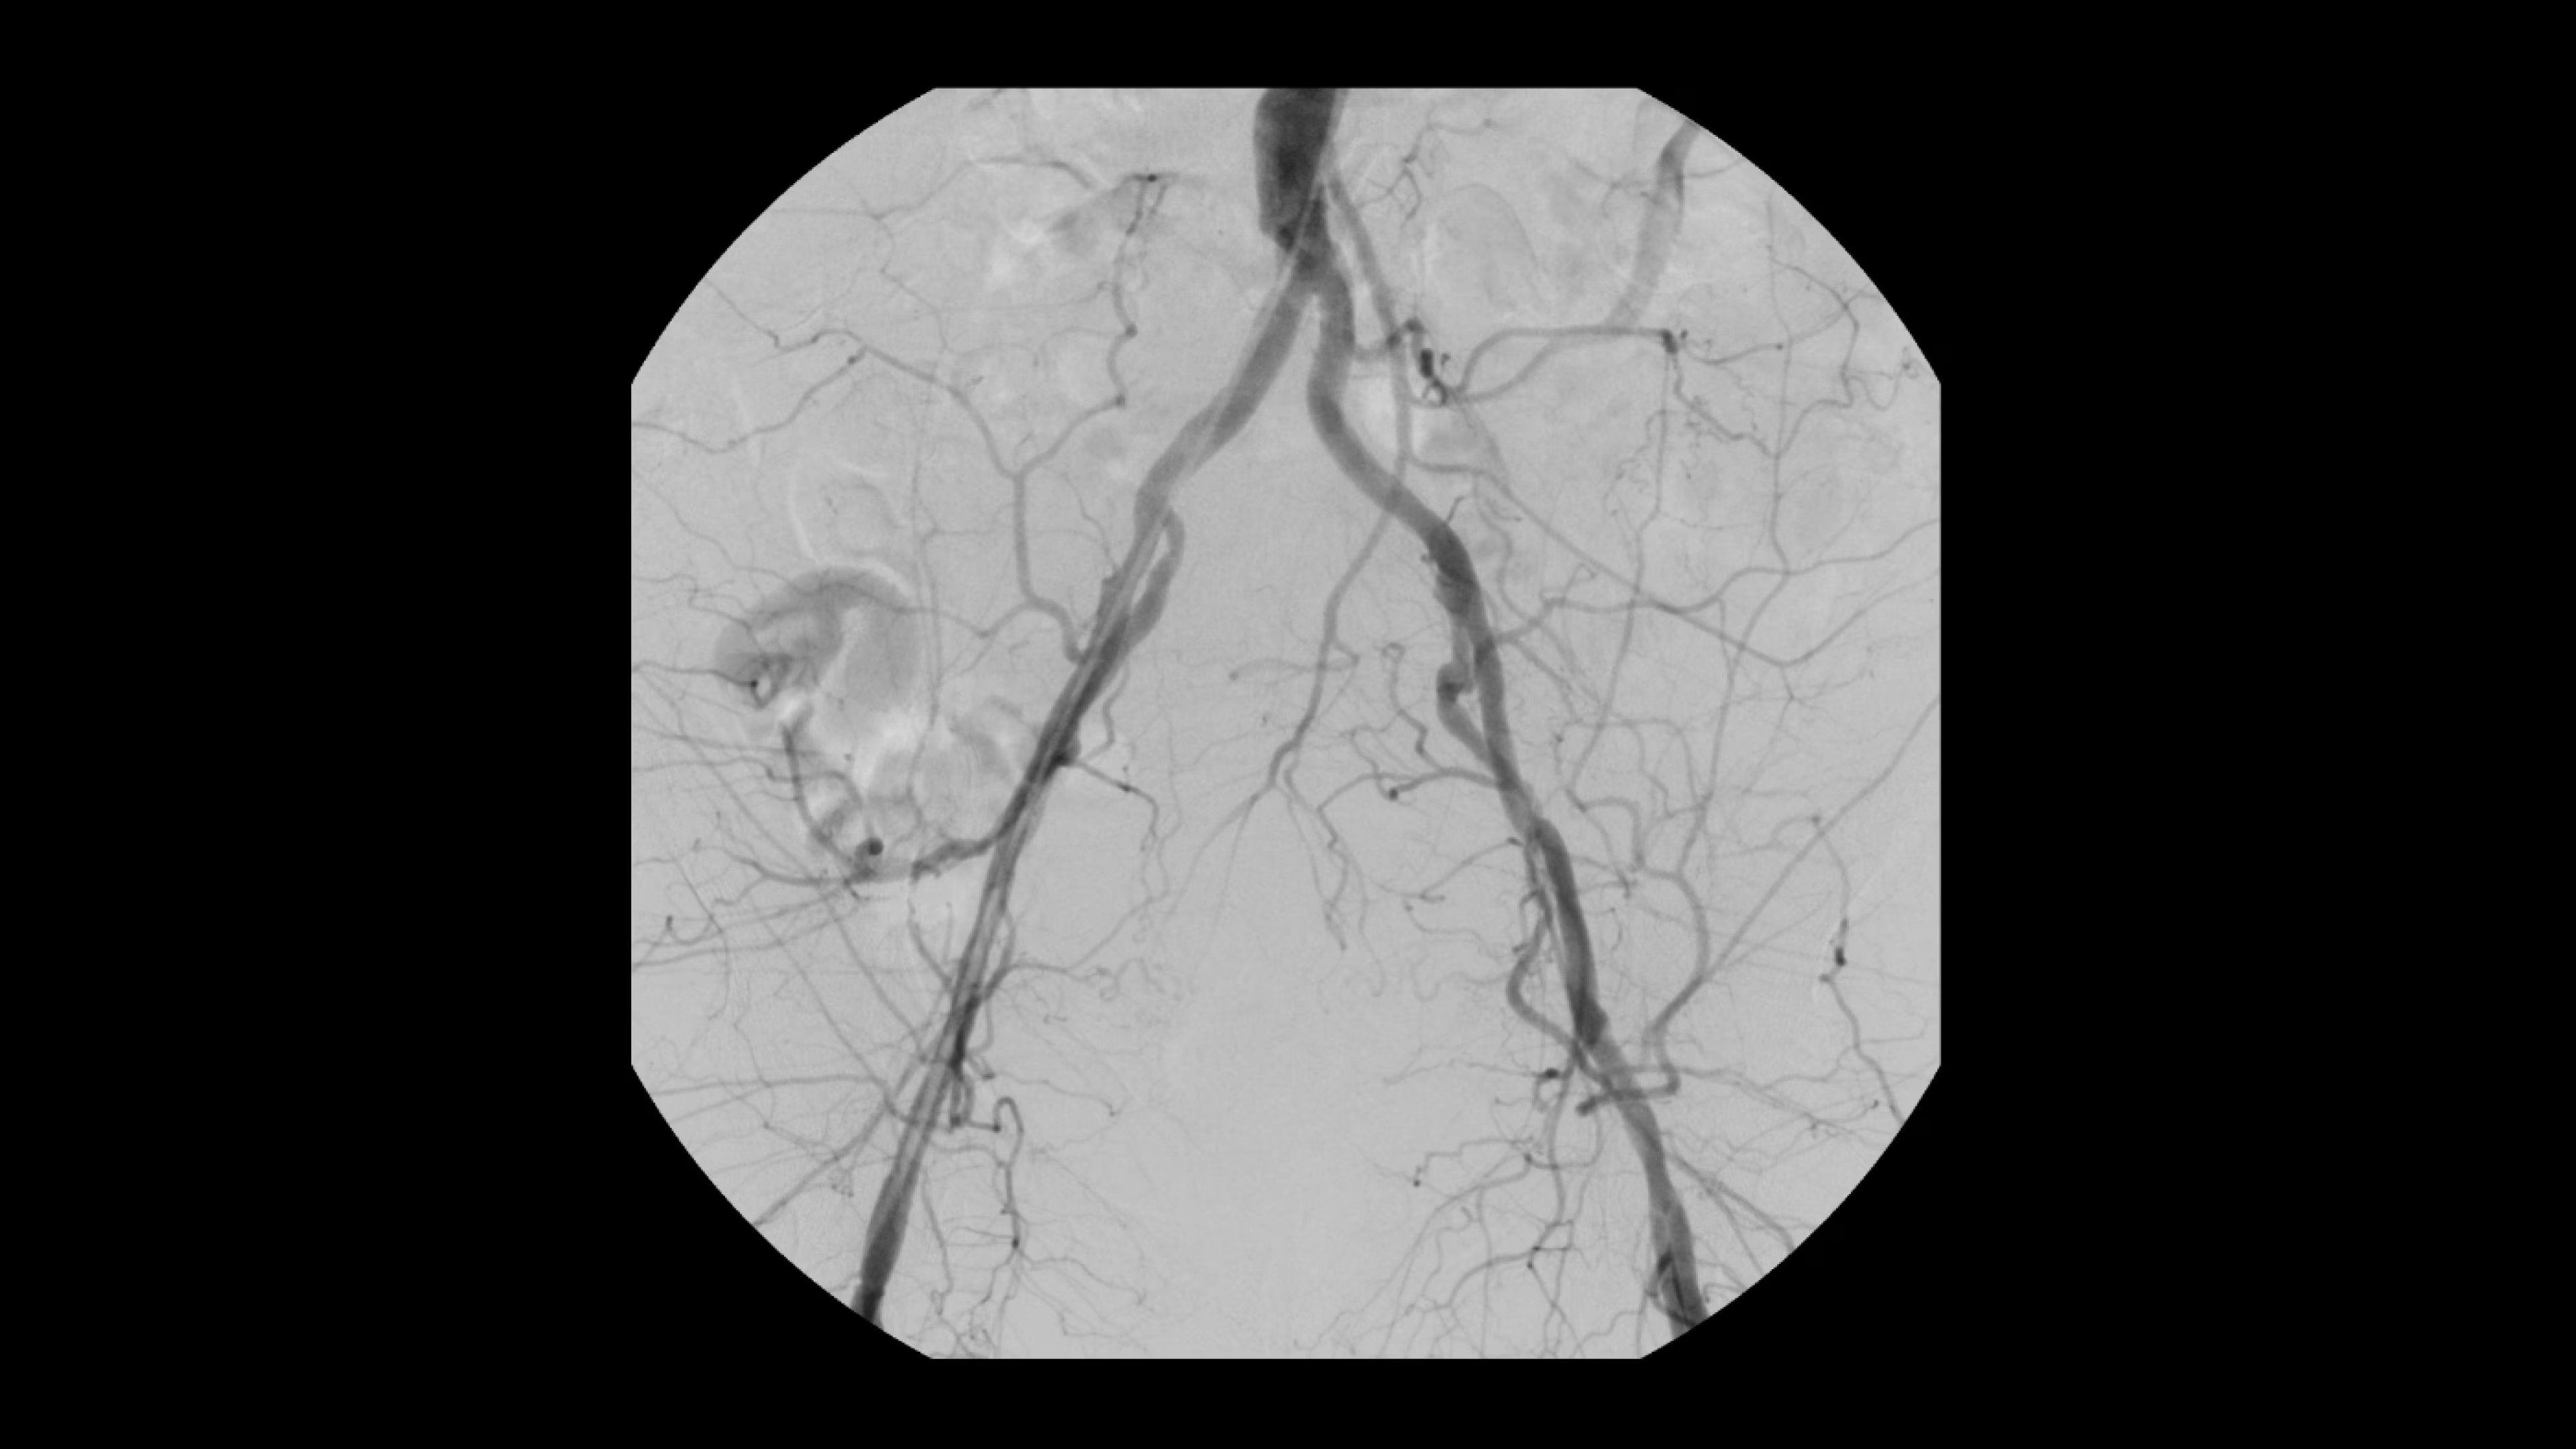

Achieve clear and detailed visualization during a variety of interventional procedures. OEC C-arms also bring efficiency to operating suites through a variety of C-arm options, including mobile cone beam CT.

See 0.014” guidewires in chest and abdomen region or 0.008” guidewires in peripheral vascular on a large 4K display.

Digitally zoom up to 4X during a fluoro shot or Cine with no change in dose by using Live Zoom.

OEC premium C-arms stay cool during long or complex interventional procedures ensuring fluoroscopy is available without interruption or degradation of imaging.